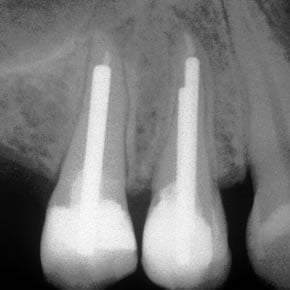

Template for x-rays

Biolight® DRILL-FREE posts are available in bundles of 4, 6, 9 and 12 strands. The post size is selected based on the width of the canal at the coronal area. Depending upon the canal width at the apical stop, a certain number of strands must be pushed to the stop. Both of the measurements are made with the assistance of a radiograph and the template that is included in the TRAINING KIT.